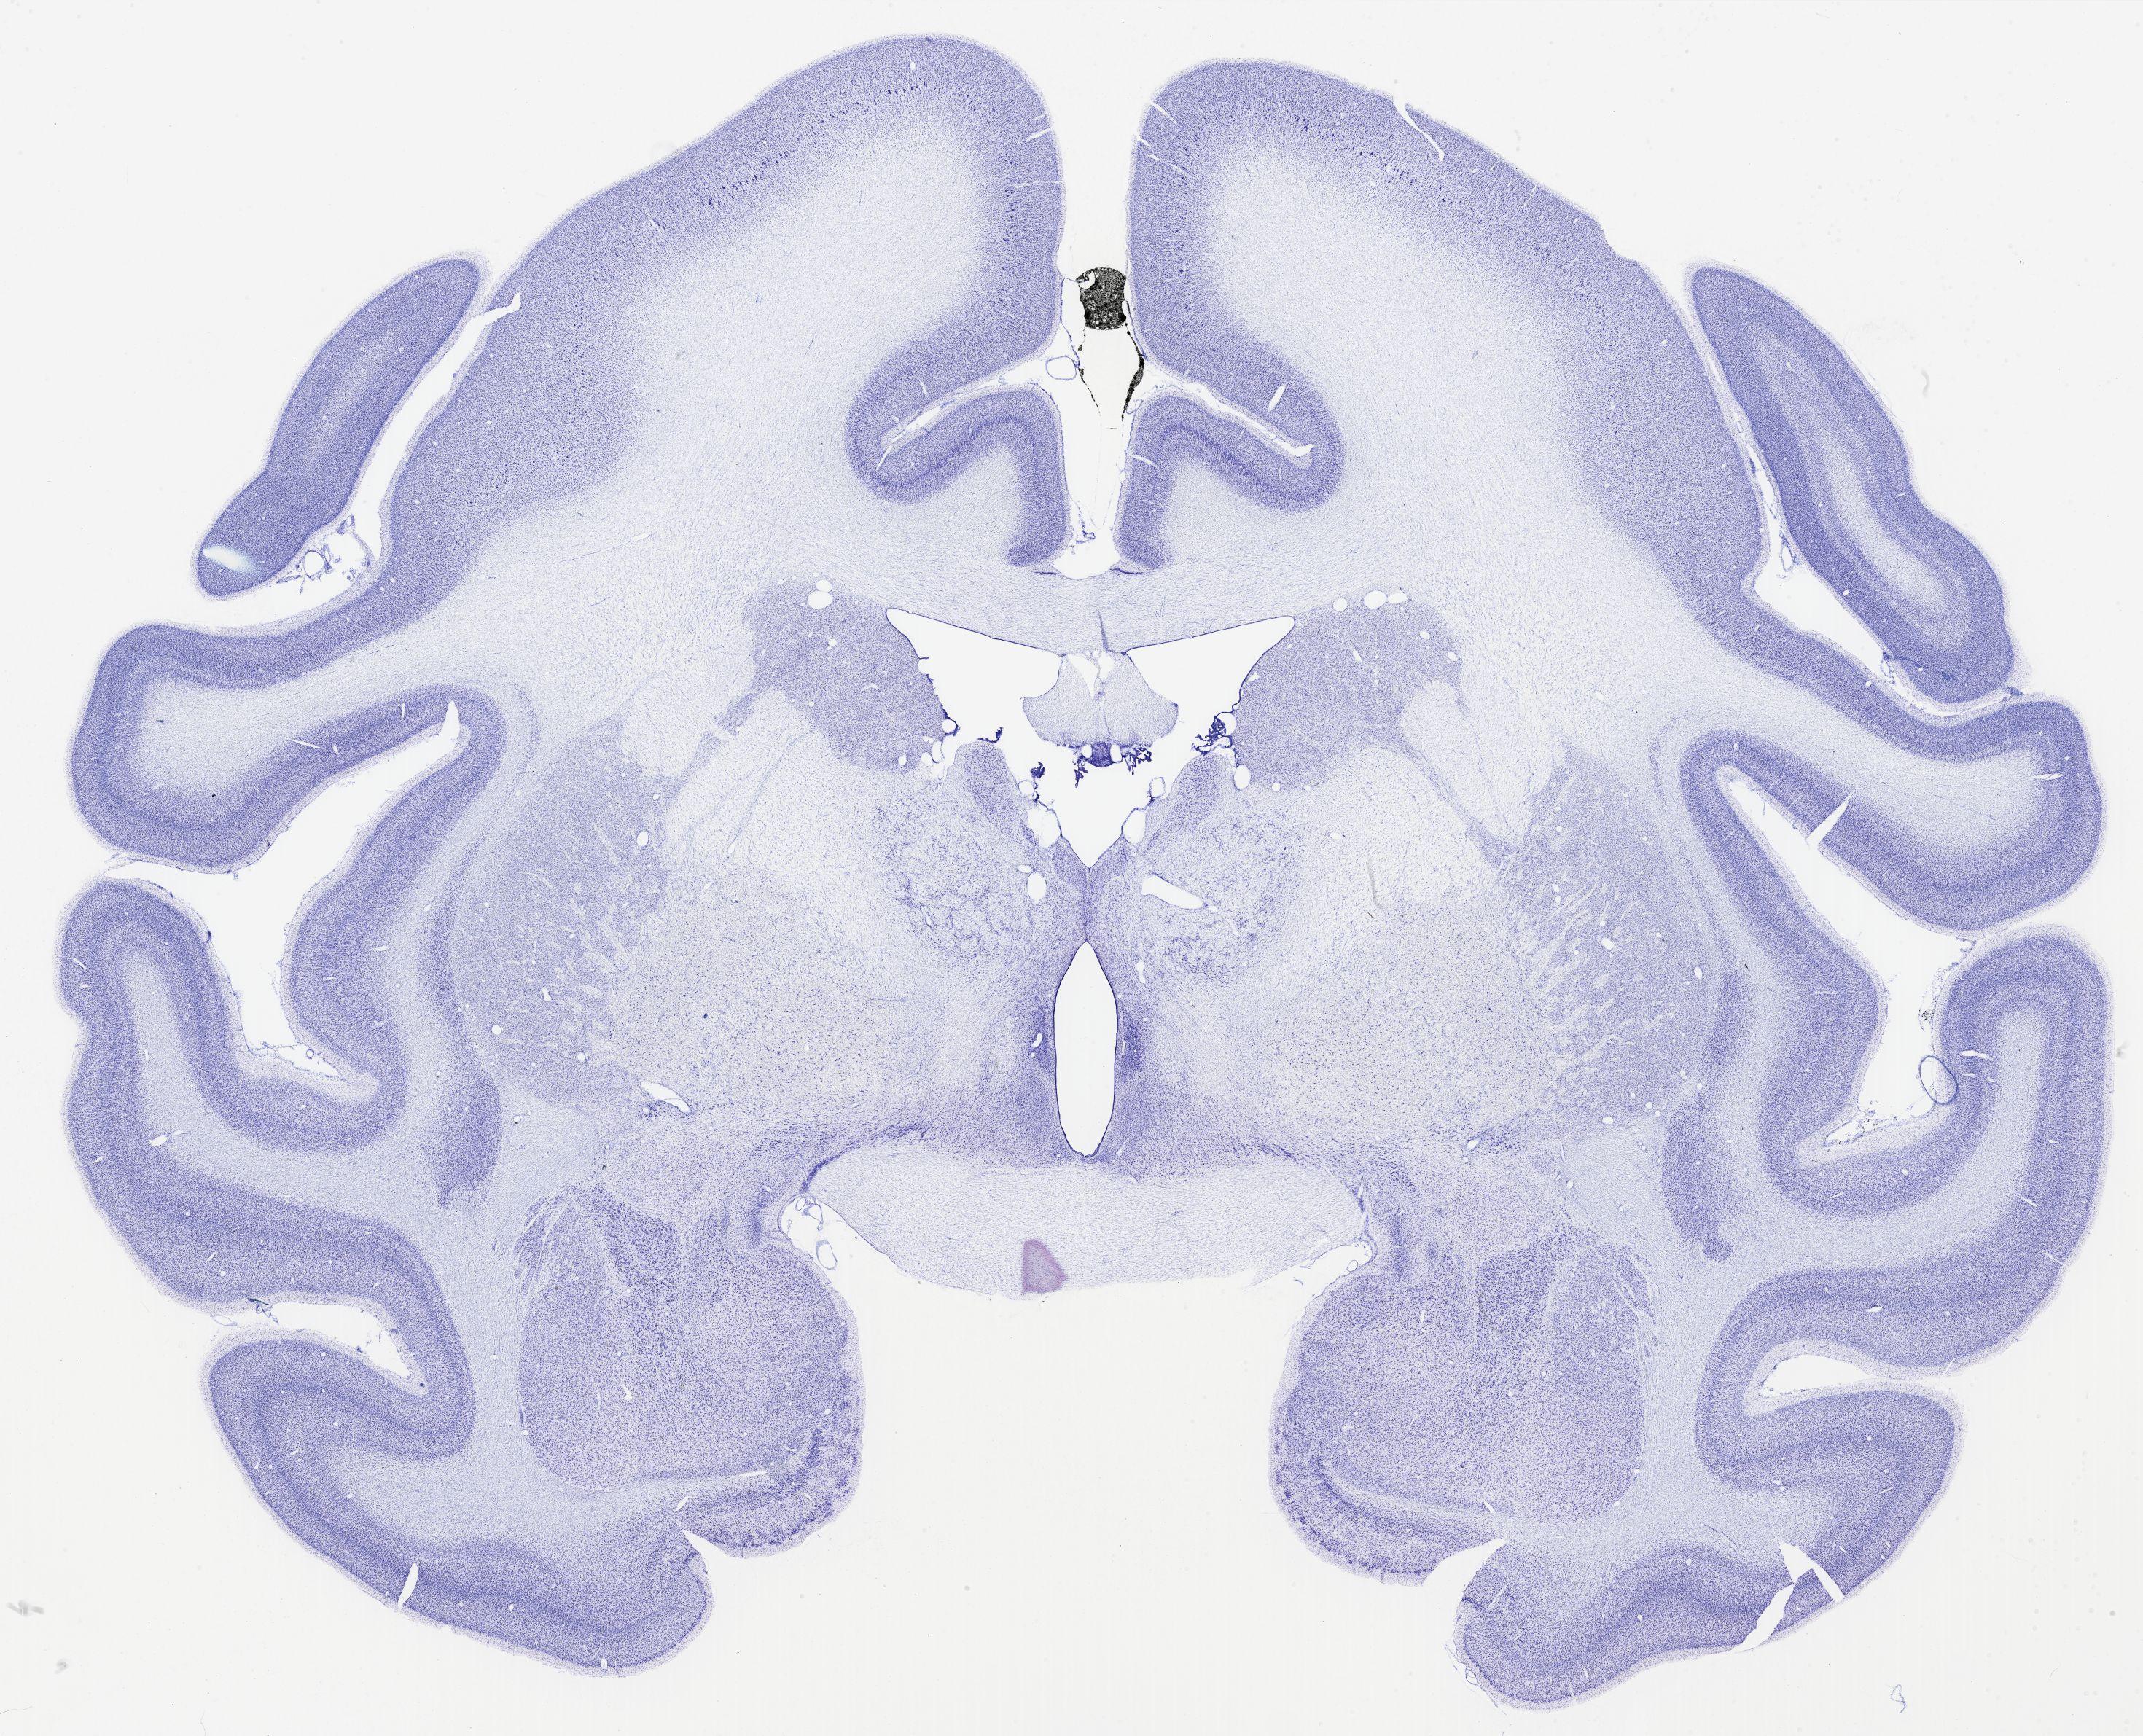

thumbnail

322